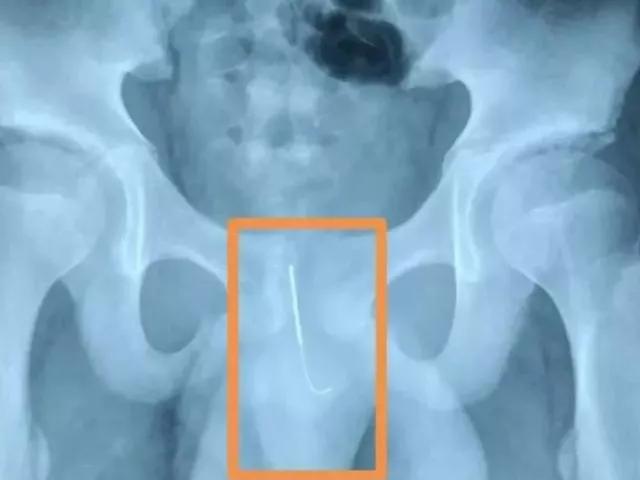

据悉,通过孩子的“骨盆平片”可以明显看到,下腹部有一个尖锐物体,尖头朝下,别说孩子家长,连医生看到这个片子,也不禁捏了一把汗!

南通海安市人民医院消化内科主任医师表示:我们接到电话,说有个小孩贪玩把飞镖从肛门放进去。这个情况一定要紧急处理,如果时间长了或者小孩运动了以后,这个飞镖一端是尖的,而且尖端朝下,正好朝向运动的方向,容易引起小肠穿孔出血或者感染。

情况紧急,孩子立即被送到医院内镜中心做肠镜。但在肠镜发现,孩子的直肠里有一个较大的粪块,沿着肠道往上探查了40公分,肠道上面很干净,医生怀疑飞镖可能在直肠的粪块里!“我们把粪块往上推,防止飞镖的尖端刺到直肠粘膜,推上去我们探查以后确认,这个飞镖没有刺到肠壁,”医生表示道。